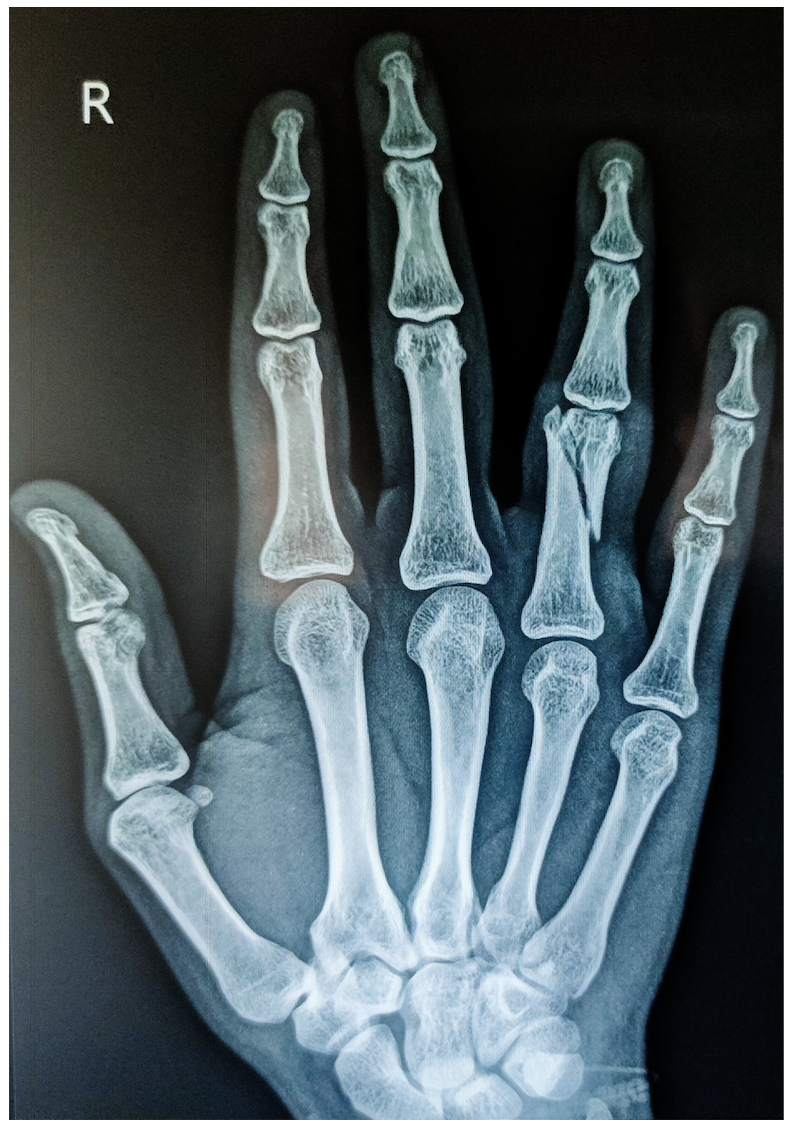

Hand fractures

Your hand contains numerous bones. When one breaks, the injury can range from a clean split creating two fragments to a shattered bone with many pieces. The overlying skin may remain unbroken (closed injury) or rupture to expose the underlying fracture (open injury).

Clinical evaluation

Assessment begins with clinical examination and radiographic imaging. Multiple variables shape the treatment blueprint: the affected bone's identity, where along its length the break occurred, degree of malalignment, whether single or multiple bones fractured, presence of additional trauma, which hand you primarily use, your work requirements, and existing medical conditions. Sometimes advanced imaging like computed tomography, ultrasound, or magnetic resonance studies clarifies the picture before determining definitive management.